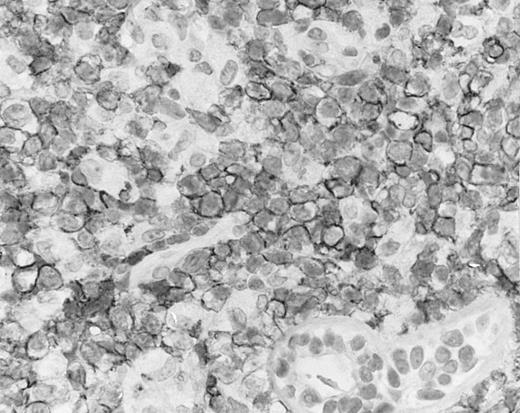

Lymph node biopsy of aggressive NK cell leukemia/lymphoma (case no. 37). There is a fairly monotonous, diffuse infiltrate of medium-sized cells with round nuclei. The neoplastic cells in this case resemble plasmacytoid monocytes.

There were very few to numerous granular lymphocytes in the peripheral blood. Some of the granular lymphocytes were indistinguishable from normal large granular lymphocytes, with round nuclei, dense chromatin, and pale cytoplasm with fine azurophilic granules (Fig 5A). Some granular lymphocytes had larger nuclei with more open chromatin and distinct nucleoli (Fig 5B); occasional nuclei could show indentations. The azurophilic granules were sometimes large and coarse. There were also circulating normoblasts and immature myeloid cells. Marrow involvement ranged from subtle to extensive. In histologic sections, irrespective of site, there was a monotonous infiltrate of medium-sized cells with round nuclei and fairly condensed chromatin (Fig 6). Karyorrhexis was prominent. The infiltrate was diffuse, interstitial, or angiocentric.